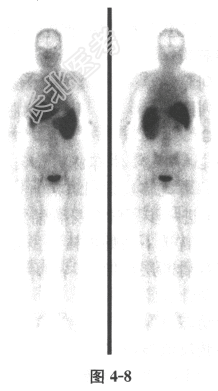

- 多项选择题3.提问3:该患者的

Tc-植酸钠骨髓显像结果见图4-8, 其类型属于

A、荒芜型

B、抑制型

C、灶Ⅰ型

D、灶Ⅱ型

E、正常型

F、以上均不是